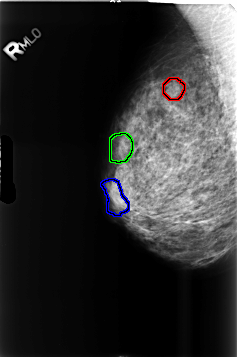

FILE: B_3460_1.RIGHT_MLO.OVERLAY

TOTAL_ABNORMALITIES 3

ABNORMALITY 1

LESION_TYPE MASS SHAPE LOBULATED MARGINS CIRCUMSCRIBED

ASSESSMENT 3

SUBTLETY 3

PATHOLOGY BENIGN

TOTAL_OUTLINES 1

BOUNDARY

ABNORMALITY 2

ABNORMALITY 3